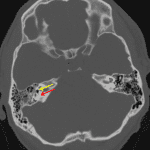

- Acute nondisplaced transverse right temporal bone fracture extending through the vestibule with gas in the otic capsule

- Anterior fracture propagation with involvement of the right carotid canal and posterior wall of the right sphenoid sinus with hemosinus

- Otic capsule involving temporal bone fracture

Extensive skull base trauma including an otic capsule involving right temporal bone fracture and occipital calvarial fractures propogating into the skull base with involvement of the right occipital condyle and extension into the right carotid canal and right sphenoid sinus. Recommend head CTA for further evaluation given carotid canal involvement.